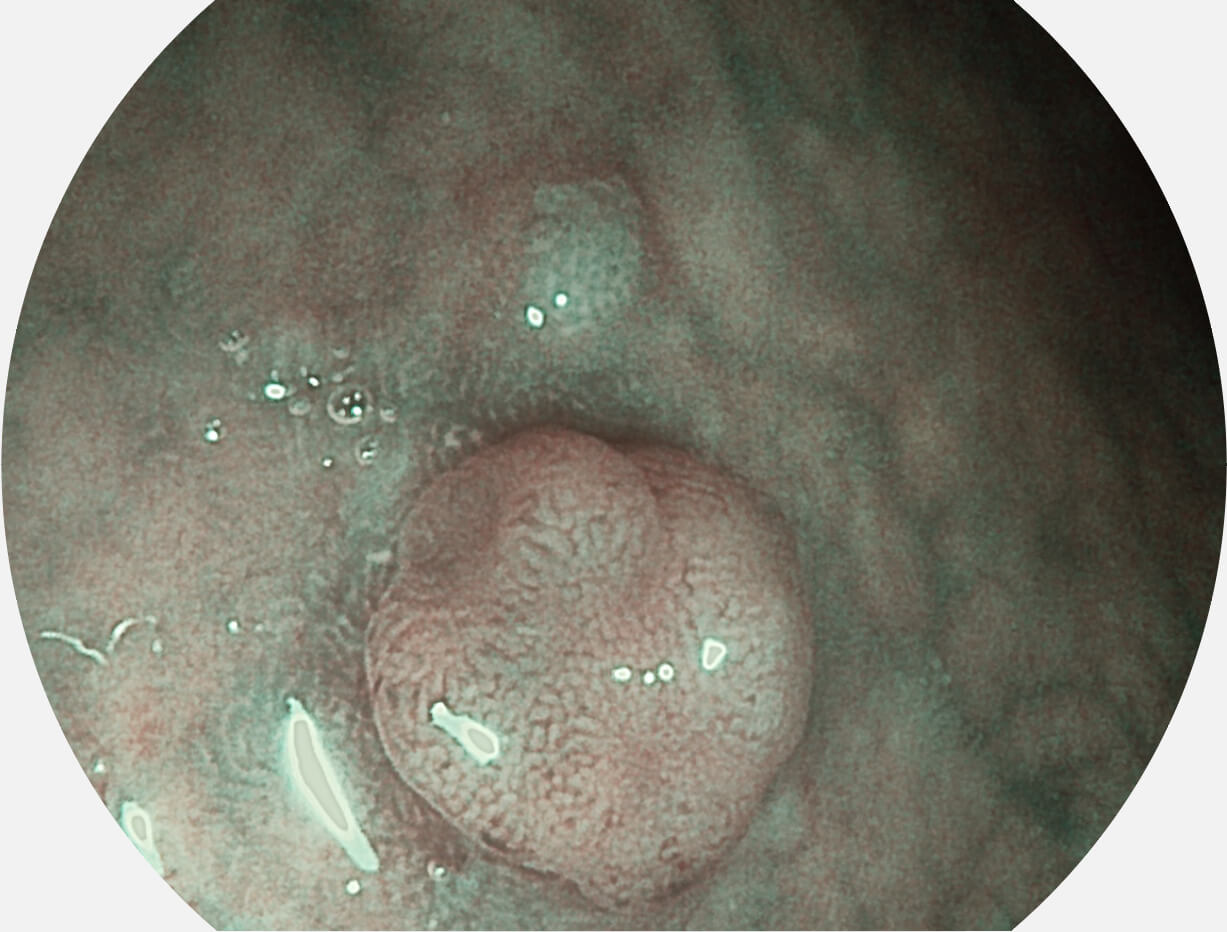

Spectral Focused lmaging, SFI

图像具有高亮度、高黏膜血管颜色对比度的特点,且不改变粘液、食物残渣、粪便的基本颜色,可在中远景下进行观察,助力消化道早期疾病的诊断。

白光图像

白光图像

SFI图像

SFI图像

白光图像

白光图像

SFI图像

SFI图像

白光图像

白光图像

SFI图像

SFI图像

白光图像

白光图像

VIST图像

VIST图像

白光图像

白光图像

VIST图像

VIST图像

白光图像

白光图像

VIST图像

VIST图像